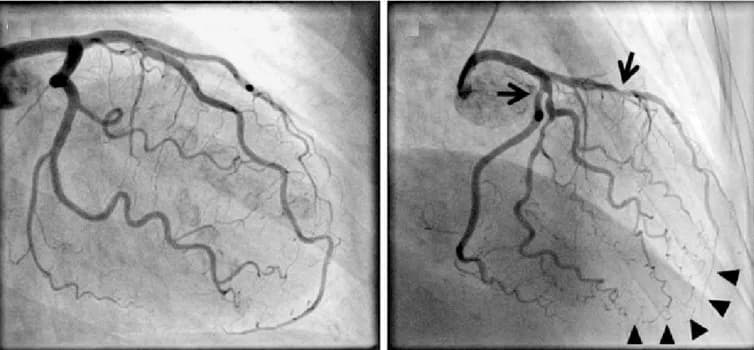

Để đánh giá tình trạng của stent và phát hiện sớm các biến chứng, chụp động mạch vành là phương pháp chẩn đoán tốt nhất. Chụp động mạch vành giúp bác sĩ quan sát trực tiếp lòng mạch và xác định xem stent còn tốt hay đã bị tắc, tái hẹp. Ngoài ra, bệnh nhân cũng cần chú ý đến các dấu hiệu bất thường và đến bệnh viện sớm hơn nếu có các triệu chứng như đau thắt ngực ngay cả khi nghỉ ngơi, tức ngực, khó thở hoặc mệt mỏi bất thường.